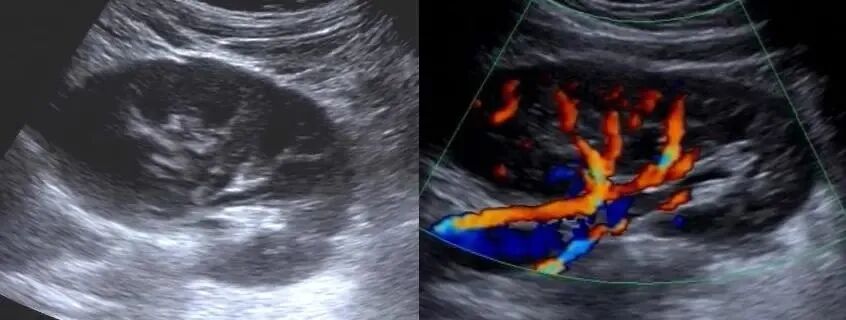

彩超即彩色多普勒血流显像(CDFI),是将所获得的多普勒运动信息进行处理,通过彩色灰阶编码,以不同的颜色和亮度分别标识血流的方向和速度的大小,并叠加于B型超声声像图上。

所谓“彩色”并不是大多数人理解的像彩色电视机一样有丰富的色彩,而是指在显示心脏和血管血流信息的时候出现的红蓝交替的图像。与黑白B超相比,彩超的分辨率更高、敏感性更强、功能更多、检查范围及内容更细、更广,可大大提高疾病诊断率,发现B超无法显示的小病灶,还能提供血流动力学信息。

(左图为黑白B超显示肾脏的结构,右图加上彩色多普勒功能清晰显示肾脏血管分布)

通常情况下,超声检查医生首先采用黑白图像探查人体组织大小、形态、边界、回声强弱等,然后再使用彩色多普勒对于血流分布情况进行分析。